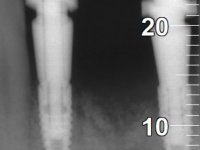

Paciente do sexo feminino com 62 anos, fumadora. 10 Anos atrás tinha sido colocado um implante na zona dos dentes 41 e 42 para reabilitar com uma ponte de dois elementos a falta destes dois dentes. Feito o exame imagiologico foi observada uma perda óssea junto ao implante compatível com uma peri-implantite. A parede óssea vestibular junto ao implante apresentava uma extensa reabsorção, estando a superfície vestibular do implante em contacto com os tecidos moles e numa determinada zona um orifício permitia a visualização do implante através do tecido gengival. Os dentes 42 e 32 apresentavam já alguma mobilidade.

Após estudo imagiológico foi planificada a colocação de dois implantes de 3.3 mm de diâmetro e 10 mm de comprimento. No dia da cirurgia foram extraídos os dentes 42 e 32 e removido o implante. Os implantes foram colocados na zona dos alvéolos tendo o cuidado de lingualizar um pouco o seu posicionamento. Foi feita uma impressão pela técnica de moldeira aberta com o retalho aberto para a confeção da ponte provisória imediata. Enquanto a impressão foi para o laboratório, foram colocados parafusos de cicatrização altos e feita a sutura da ferida cirúrgica. A paciente esperou 2 horas na sala de espera enquanto no laboratório era confecionada a ponte provisória. A ponte provisória imediata aparafusada foi colocada e o seu assentamento controlado imagiologicmente. Passados 3 meses foi realizada a impressão definitiva com uma técnica de moldeira aberta. Nessa consulta aproveitamos para polir a ponte provisória com taças de borracha para que os tecidos moles pudessem maturar em melhores condições. Foi feita a recolha de informação para caracterizar da melhor forma a estrutura monolítica em Zr. Foram utilizadas guias de cor para a cerâmica de tonalidade coronária e gengival. No laboratório foi confecionada uma ponte em Zr. aparafusada que foi cuidadosamente caracterizada. Após aprovação pela paciente foi colocada definitivamente em boca. O aperto foi feito com uma chave dinâmica com 35 N de torque. Os orifícios foram tapados com teflon e obturados com resina composta.